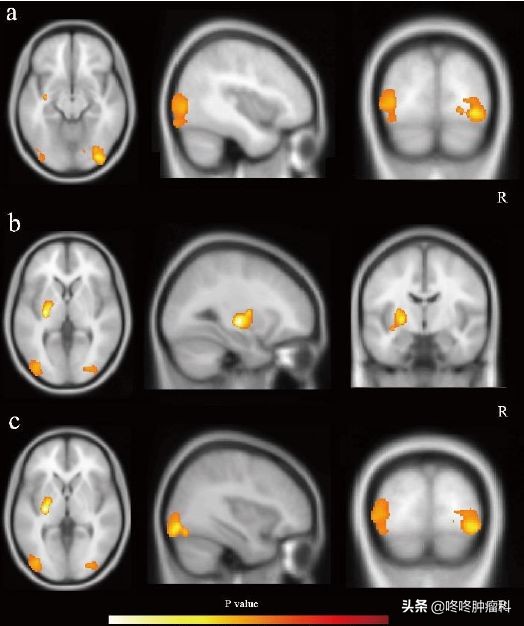

与此同时,宫教授带领的团队,也发现相比于服药前,患者长期服药后,右枕叶、左枕叶以及左侧基底节区的脑灰质体积明显下降(下图黄色符号圈出了受影响的区域);既往研究显示:这些区域的脑灰质与认知功能等重要的大脑功能密切相关。